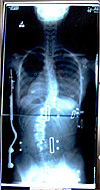

装具装着立位後方写真を見ていただくと一目瞭然です。

この写真は大阪医科大学装具です。

| (a) |

(b) |

左記の写真の如く(a)は左腰椎湾曲(b)右胸椎湾曲

しかし、装具は大阪医科大方式で同じタイプ。

湾曲が腰椎でも胸椎でも同じ装具であり

Wカーブでも同じ装具です。

この装具装着姿を見ていただければわかるように左腰椎湾曲、右胸椎湾曲でも同じ装具である、

しかも、パッドがないこのタイプの欠点を述べますと下記の通りです。